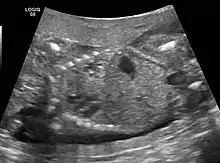

CPAMs are often identified during routine prenatal ultrasonography. Identifying characteristics on the sonogram include: an echogenic (bright) mass appearing in the chest of the fetus, displacement of the heart from its normal position, a flat or everted (pushed downward) diaphragm, or the absence of visible lung tissue.

Imaging

The earliest point at which a CPAM can be detected is by prenatal ultrasound. The classic description is of an echogenic lung mass that gradually disappears over subsequent ultrasounds. The disappearance is due to the malformation becoming filled with fluid over the course of the gestation, allowing the ultrasound waves to penetrate it more easily and rendering it invisible on sonographic imaging. When a CPAM is rapidly growing, either solid or with a dominant cyst, they have a higher incidence of developing venous outflow obstruction, cardiac failure and ultimately hydrops fetalis. If hydrops is not present, the fetus has a 95% chance of survival. When hydrops is present, risk of fetal demise is much greater without in utero surgery to correct the pathophysiology. The greatest period of growth is during the end of the second trimester, between 20–26 weeks.

A measure of mass volume divided by head circumference, termed cystic adenomatoid malformation volume ratio (CVR) has been developed to predict the risk of hydrops. The lung mass volume is determined using the formula (length × width × anteroposterior diameter ÷ 2), divided by head circumference. With a CVR greater than 1.6 being considered high risk. Fetuses with a CVR less than 1.6 and without a dominant cyst have less than a 3% risk of hydrops. After delivery, if the patient is symptomatic, resection is mandated. If the infant is asymptomatic, the need for resection is a subject of debate, though it is usually recommended. Development of recurrent infections, rhabdomyosarcoma, adenocarcinomas in situ within the lung malformation have been reported.[4]